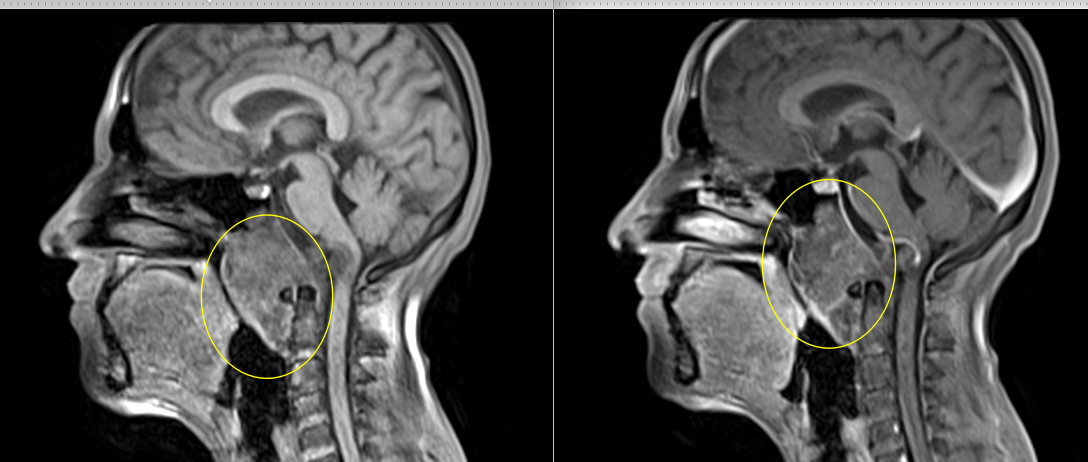

A. Imagistică:

- CT cranian cu reconstrucție 3D: evidențiază detalii osoase.

- RMN cerebral cu contrast: evaluează extensia intracraniană, vasele și nervii implicați.

C. Cordomul

Tumoră rară, malignă, ce derivă din resturi embrionare ale notocordului.

Apare frecvent la nivelul clivusului (baza craniului).

Se dezvoltă lent, dar are potențial invaziv.

Simptome: durere, pareze oculomotorii, tulburări de deglutiție.

Tratament: rezecție chirurgicală maximală + radioterapie stereotactică – protonoterapia sau radioterapia cu ioni de carbon.

B. Condrosarcomul

Tumoră malignă ce derivă din țesut cartilaginos.

Frecvent localizat la baza craniului (clivus, sfenoid).

Simptome: cefalee, diplopie, afectarea nervilor cranieni.

Creștere lentă, dar invazivă.

Tratament: excizie chirurgicală completă + radioterapie postoperatorie.